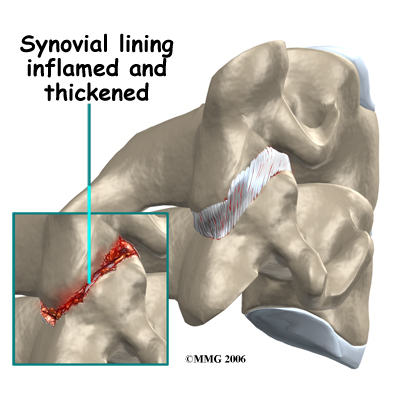

In RA, the synovial lining of the joint is affected. The normally thin tissue of the synovial lining becomes inflamed and thickened. This material begins to produce inflammatory chemicals that damage the articular cartilage and bone underneath. The joint is slowly destroyed until bone rubs against bone. In the spine, there are synovial joints between each vertebra and between the skull and the first cervical vertebra. With so many synovial joints in the spine, it is obvious why patients with RA often feel the disease there, and why it is categorized as a spondyloarthropathy.